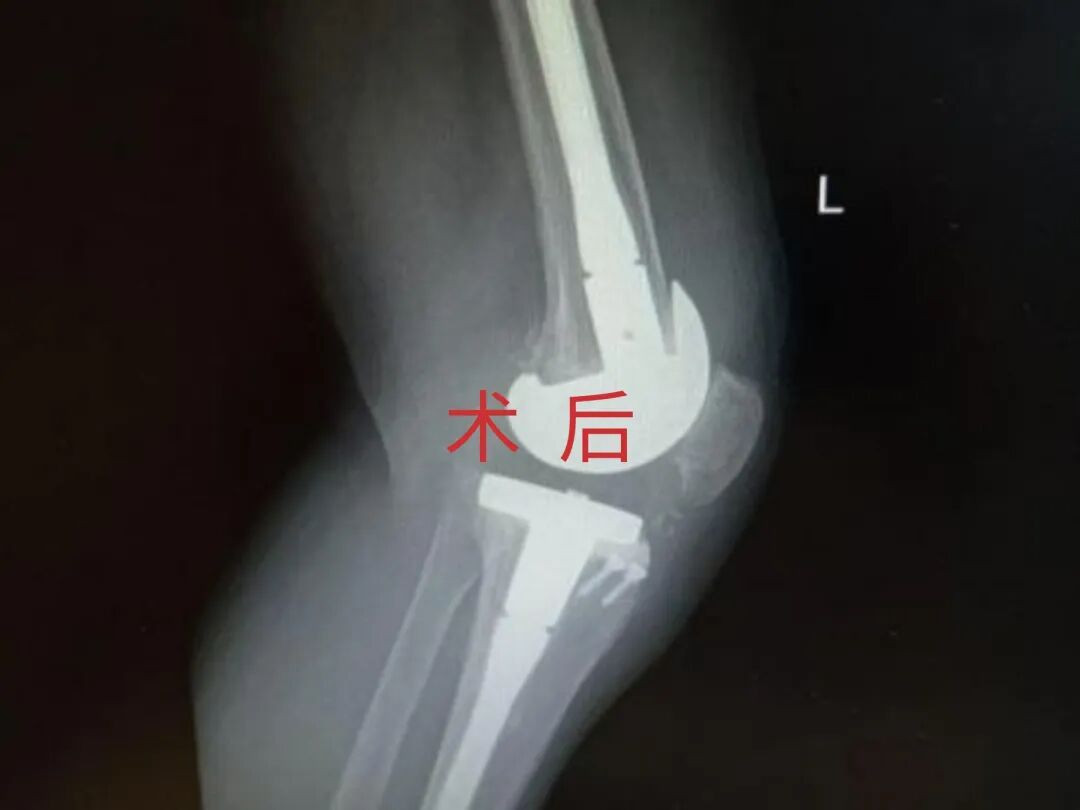

4月23日,贵州航天医院第58次晨读会由我院骨科副主任医师张艳金作学术交流,他以“加速康复指导下的快速手术”为题,详细讲解了老年股骨粗隆间骨折与儿童四肢骨折的临床诊疗难点,结合加速康复外科(ERAS)核心理念,重点阐述了ERAS理念在两大人群中的创新实践,实现患者入院后6至24小时内即可接受手术治疗。针对老年髋部骨折患者,提出通过多学科协作(MDT)与微创手术优化围术期管理,在确保安全前提下缩短术前等待时间,实施精准化麻醉及术后康复方案,可有效降低并发症发生率、改善患者生活质量和预后效果。在儿童骨折领域,强调微创术式与心理干预并行的双轨策略,既减少手术创伤对骨骼发育的影响,同时关注患儿心理疏导,实现生理功能与心理健康同步康复。并通过典型案例的影像学资料与随访数据,直观展示了ERAS理念指导下骨科治疗模式的创新成果。 贵州航天医院骨科 专家简介 赵学平 中共党员,骨科党支部书记、主任,主任医师 临床擅长:从事骨科临床工作30余年,对骨科常见疾病的诊治具有丰富的临床经验。 世界中医药联合会脊柱康复专业委员会常务理事,中华中医药学会整脊分会常务委员,中国中西医结合学会骨伤科分会肢体矫形功能重建与康复专家委员会常务委员,中国研究性医院学会骨科创新与转换专业委员会关节外科学组保髋工作委员会常委,中国康复技术转化及发展促进会骨外科与康复技术转化专业委员会常务委员,泛珠三角区域运动医学联盟(PPRD-SMA)理事会常务理事,中国研究型医院学会运动医学专业委员会委员,贵州省中医药学会整脊分会副主任委员,贵州省中西医结合学会银质针专业委员会副主任委员,贵州省康复医学会骨与关节专业委员会常务委员,贵州省人民医院骨科专科联盟常务理事,贵州省康复医学会骨内科专业委员会常务委员,中华医学会贵州省骨科学会委员,贵州省康复医学会脊柱脊髓专业委员会常务委员,贵州省运动医学分会委员,贵州省康复医学会骨与软组织肿瘤专业委员会委员,遵义市医学会创伤分会副主任委员,贵州省康复医学会骨内科专业委员会遵义地区分会常务委员,遵义市医疗事故鉴定、伤残鉴定、工伤鉴定、司法鉴定专家。 长期从事骨科临床研究及教学工作,在国家级、省部级杂志发表论文20余篇,SCI论文2篇,参与主编骨科专著2部,主持省部级科研项目2项,参与指导省部级、市级科研项目6项。 陈明勇 骨科副主任,副主任医师 临床擅长:从事创伤骨科工作约20年,对骨缺损、骨不连、骨肿瘤、肢体畸形等的肢体矫形重建及功能重建,慢性化脓性骨髓炎的根治治疗、糖尿病足的保肢治疗、快速康复理念(ERAS)下的老年骨折的诊治,四肢复杂骨折的诊治,四肢骨折等微创手术治疗具有丰富的临床经验。 2004年毕业于遵义医学院临床专业,曾在中国人民解放军总医院、广西医科大学第一附属医院、上海第六人民医院骨科进修。中国中西医结合学会骨伤科专业委员会横向骨搬移治疗糖尿病足及微血管网再生学组首届委员,遵义市医学会创伤分会常务委员。 瞿 辉 中共党员,骨科副主任医师 临床擅长:对骨科的常见病、关节外科、脊柱外科及运动医学疾病的诊治具有丰富的临床经验,熟练掌握骨科手术操作技术。 毕业于遵义医学院临床医学系,2005年前往广州中山大学第一附院骨显微医学部进修学习,2011年前往成都华西医院进修学习,并多次在省内外学习骨科相关知识,是中华医学会骨科分会会员。 赵兴东 骨科主任医师 临床擅长:擅长骨科的常见病及各种创伤、四肢骨折创伤修复、骨感染、手足疾病的诊治和手足体表畸形的矫形整复,熟练掌握骨科四肢骨病及创伤的手术操作技术,尤其在四肢关节复杂性损伤、手足外伤、组织缺损创面、难治创面的皮瓣修复方面及平足、高弓足矫形方面及四肢慢性疼痛诊治、康复方面具有丰富的临床经验。 硕士研究生,毕业于遵义医学院临床外科系,2015年前往山东省立医院手足外科进修学习;遵义市医学分会创伤分会第一、二届委员,遵义市手外科医学会第二委届员会常务委员;在省级及省级以上期刊发表文章9篇,参编著作2部,参与主持并完成市级课题1项,参与市级课题2项、省级课题1项。 张艳金 中共党员,骨科副主任医师 临床擅长:从事骨外科工作16年,对复合伤、多发伤的救治、四肢骨干骨折、关节周围骨折、骨肿瘤、骨髓炎等诊治具有丰富的临床经验。 中共党员,硕士研究生,2006年本科毕业于山西医科大学第二临床医学院,2011年研究生毕业于北京军区总医院;在“老年COPD患者合并髋部骨折的诊治”国际合作课题组研究两年,在老年髋部骨折的诊治方面具有丰富的经验,并发表论文6篇;主持遵义市级课题1项,承担遵义医科大学的临床教学工作,获得遵义医科大学优秀带教老师荣誉。编撰有《骨科疾病诊疗精粹》一书,开展2项新技术,编撰地方规范《务川自治县创伤骨科常见疾病诊疗规范》一书。 张俊凯 骨科副主任医师 临床擅长:从事骨科临床工作28年,对创伤骨折、骨感染、骨缺损、骨不连等外科诊治,四肢骨折的微创手术治疗,四肢复杂骨折(如关节内粉碎性骨折、多发骨折等)的损伤控制及手术治疗等具有丰富的临床经验。 1995年毕业于遵义医学院临床专业,2009年前往复旦大学附属医院骨科进修1年。 卢懿明 中共党员,骨科副主任医师 临床擅长:从事骨科工作18年,对创伤骨折、四肢骨折的微创手术治疗、四肢复杂骨折(如关节内粉碎性骨折、多发骨折等)的损伤控制及手术治疗,尤其是髋部骨折的PFNA等微创技术,踝关节骨折、膝关节周围骨折的Mipo微创技术等具有丰富的临床经验,开展了4项新技术,发明6项新型专利技术。 2005年毕业于遵义医学院临床专业,2017年,前往南方医科大学第三附属医院骨科进修半年,回院后运用Mipo技术对骨干骨折及干骺端骨折的治疗技术,同时积极开展骨盆骨折、髋臼骨折腹直肌外侧切口的应用;发表了多篇专业论文,经常参与省内外学术交流会授课,获得医院荣誉称号多个。 邬夏荣 骨科副主任医师 临床擅长:从事骨科工作16年,对四肢复杂骨折、骨肿瘤的诊治,尤其是足踝创伤、慢性踝关节损伤、平足症等诊疗具有丰富的临床经验。 2006年毕业于遵义医科大学临床医学专业,曾在陆军军医大学西南医院进修学习,发表多篇骨科学术论文。 余德怀 中共党员,骨科副主任医师 临床擅长:从事骨科工作10余年,对运动医学、骨关节、脊柱外科常见病、多发病的诊治具有丰富的临床经验。 硕士研究生,2011年毕业于遵义医学院临床医学专业,曾前往遵义医科大学附属医院运动医学专业进修学习;是贵州省医学会运动医学分会青年委员,西部关节镜联盟委员;发表多篇骨科学术论文。 冯 乾 骨科副主任医师 临床擅长:从事骨科工作近20年,熟练掌握骨科多发病及常见病的诊治,尤其对脊柱退变性疾病的诊断及治疗具有丰富的临床经验,主要研究脊柱微创相关治疗方式,能熟练开展椎间孔镜及UBE。 曾前往北京大学第三医院进修学习疼痛及椎间孔镜、首都医科大学友谊医院专业进修脊柱内镜;是贵州省康复医学会第三届脊柱脊髓专业委员会委员;发明专利3项、发表脊柱外科专业论文多篇。 赵小锋 中共党员,骨科副主任医师 临床擅长:从事骨科临床工作11年,对骨科常见病、多发病诊疗有较为丰富的临床经验,擅长脊柱相关疾病诊断及治疗,尤其是颈、腰、腿疼痛疾病诊断及治疗,擅长胸腰椎骨折微创经皮穿刺内固定术、经皮穿刺椎体成形术、经皮穿刺脊柱内镜下腰椎间盘摘除术、单纯开创腰椎间盘摘除术、腰椎滑脱复位椎间植骨椎融合内固定术、腰椎管狭窄减压融合内固定术及人工髋、膝关节置换术等。 2012年毕业于遵义医学院外科学专业硕士研究生,2019年参加“遵义市115医学人才精英计划”于上海交通大学第一附属医院培训学习,2023年于北京大学第三人民医院脊柱外科进修学习,曾获得遵义市优秀医师荣誉称号。 遵义市手外科第一届委员,遵义市医学会创伤分会第一届委员,遵义市医学会创伤分会第二届委员,贵州省康复医学会第三届脊柱脊髓专业会委员,遵义市医学会烧伤与整形外科学分会委员,发表论文5篇,其中国家级核心期刊1篇,SCI论文1篇,主持市级课题1项并结题,参与市级课题2项。 贵州航天医院骨科 简介 基本情况 贵州航天医院骨科组建于20世纪60年代,前身是以创伤和断肢(断指)再植闻名于世的上海市第六人民医院骨科,中国断肢(断指)再植的奠基者、中科院院士陈仲伟等著名专家、学者多次莅临科室指导医疗、教学,是贵州省最早拥有专业骨科技术科室之一,在70年代开展了贵州省首例断肢(断指)再植手术。组建50余年来,诊治患者已逾百万,挽救了无数的伤病员,成为了保障遵义地区人民群众健康的重要支撑。 经过几代人的不懈努力,今天的骨科,已由创伤骨科发展至骨病、骨肿瘤、骨结核等领域,现有脊柱外科、关节外科、四肢创伤、手足外科四个亚专科,成为了集医疗、教学、科研于一体的综合学科,是贵州省临床重点专科、遵义市临床重点专科、遵义市骨科临床医学中心、遵义市基层骨科专科联盟理事长单位。 科室目前开放床位110张,共有医护人员50余人,副高级以上专家18人,硕士研究生15人。拥有一流骨科医疗设备多台,每年不定期选派优秀技术骨干到全国各大知名医学院校进修、学习、参观、交流,并邀请国内、国外知名专家教授来院进行交流、指导,通过不断引进国内外先进的诊疗技术,科室医疗技术水平稳步提升,为广大人民群众提供了优质的医疗服务。 专科特色 骨一科 (一)骨缺损、骨不连的肢体与功能重建 胫骨横向骨搬移技术治疗糖尿病足: (二)慢性骨髓炎的根治治疗 (三)肢体缺血性疾病如糖尿病足、脉管炎的保肢治疗 (四)皮瓣修复 (五)复杂创伤的治疗 (六)老年髋部骨折及小儿骨折快速手术 老年髋部骨折: 骨二科 (一)胸腰椎骨折微创经皮椎弓根螺钉固定术 (二)老年性骨质疏松性患者腰椎滑脱脊柱内固定术(骨水泥螺钉) (三)V形双通道脊柱内镜技术(VBE)腰椎融合术治疗腰椎退行性疾病 (四)老年性骨质疏松性骨折(PVP/PKP)术 (五)人工髋关节置换术 (六)双侧股骨头坏死人工全髋关节置换 (七)右侧全髋置换术后假体周围骨折翻修 (八)人工膝关节置换术 (九)人工膝关节假体松动翻修 (十)关节镜技术 传统手术切口 关节镜技术切口 诊疗范围 骨一科 1.四肢创伤、矫形。 2.手、足踝外科。 骨二科 end